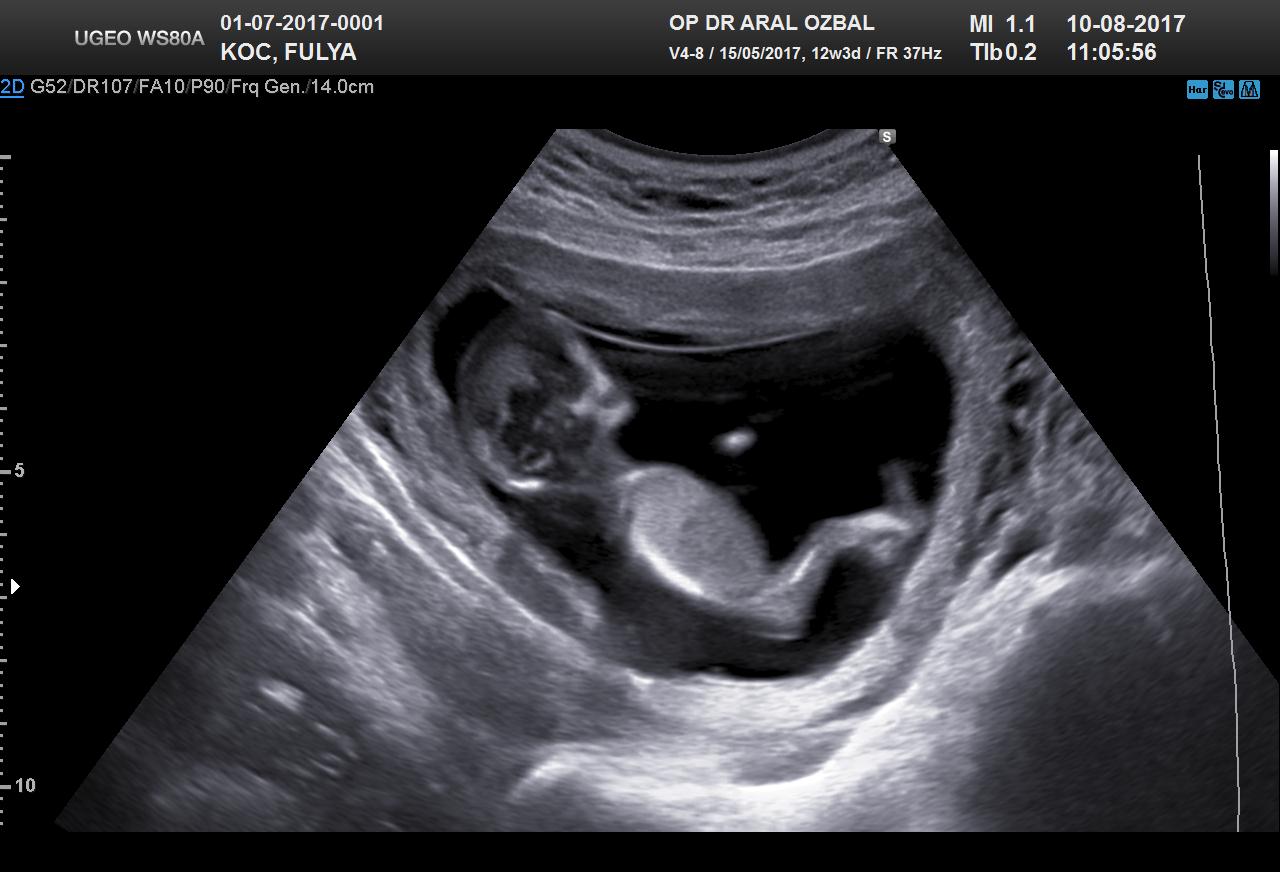

B Baharr@86 Forum Okuru 14 Ağustos 2017 #27 Benimkinede bakabilirmisiniz. 12+3 haftalık Ekli dosyalar 20170810111903_967.jpg 94,5 KB · Görüntüleme: 946 20170810111903_390.jpg 69,9 KB · Görüntüleme: 927

Uzman SühaN Administrator 14 Ağustos 2017 #28 Merhaba nub teorisine göre bebeğin poziyonu yan olmalı . Uygun görsele sahip değilsiniz bu yüzden değerlendirme yapamıyoruz.

Merhaba nub teorisine göre bebeğin poziyonu yan olmalı . Uygun görsele sahip değilsiniz bu yüzden değerlendirme yapamıyoruz.